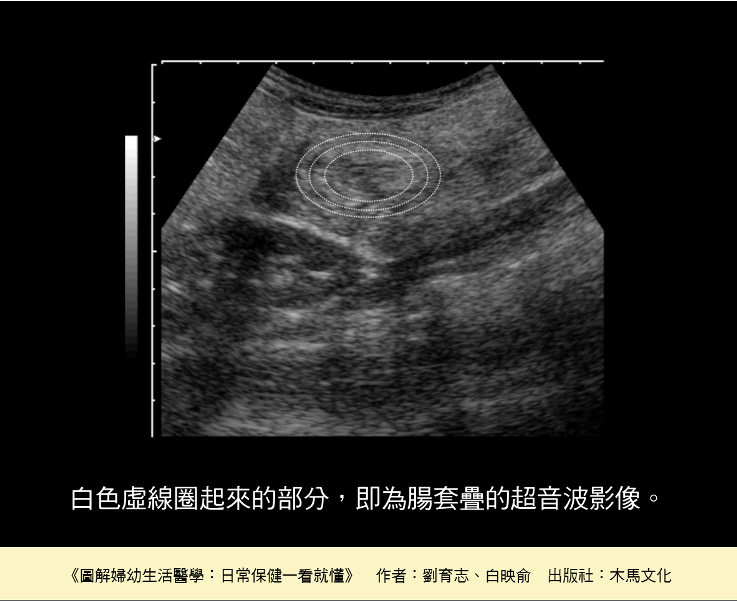

當醫師懷疑小病人罹患了腸套疊,通常會安排腹部超音波,若能找到類似「甜甜圈」或「標靶」的影像,就是腸子套疊在一塊兒,需要儘快處理。超音波的準確性很高,但是假使小病人嚴重脹氣或持續哭鬧無法配合,便很難進行檢查。